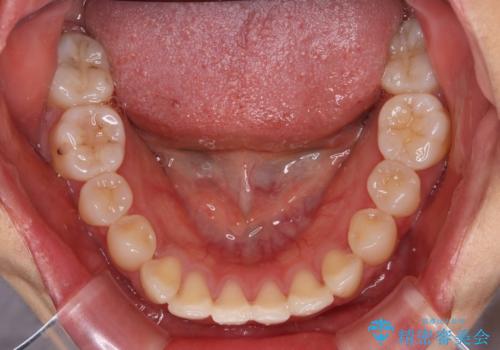

- 左上の前歯のがたつきを主訴に来院された患者様です。

上顎歯列が下顎の歯列に対して狭小であり、一部下顎の奥歯が上顎よりも外側に位置している状態でした。

上顎の歯列を拡大しスペースを設け、さらに左上の小臼歯を一本抜歯し左上の八重歯を歯列内に入れ整えていくことにしました。